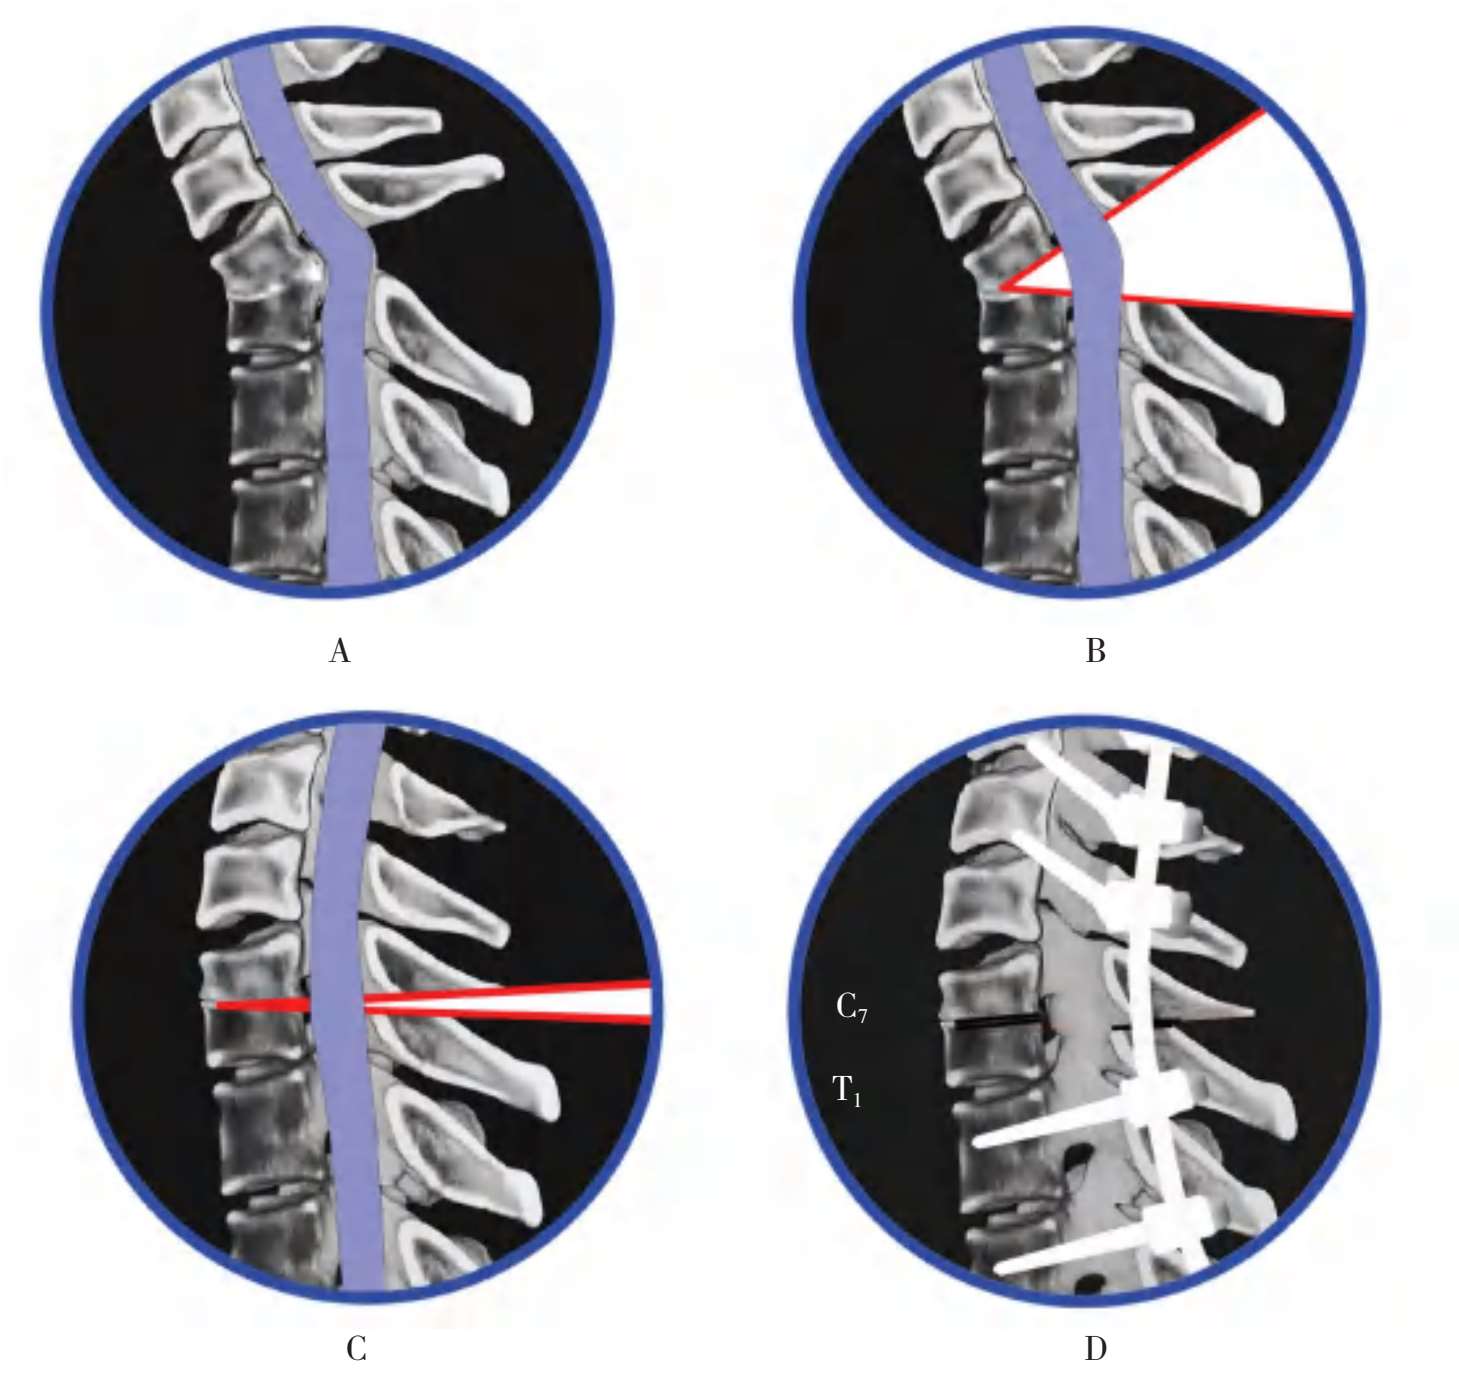

A.术前颈胸段后凸畸形47°;B.椎弓椎体次全截骨术的角度40°;C.截骨矫正闭合复位后,后凸角变为3°;D.内固定置入后,后凸角变为0°

图2-67 结核性颈胸段后凸畸形椎弓椎体次全截骨术及内固定术

(1)结核性后凸与强直性脊柱炎后凸的内固定方法有所不同,8~12岁儿童的颈胸段脊柱后凸与成年人的颈胸段脊柱后凸也有所不同。强直性脊柱炎的棘突骨化增厚,棘间韧带及棘上韧带形成骨化强直,有利于做棘间固定,其把持力甚大,是有力内固定选择部位。而儿童颈胸段结核的棘突常常发育得还不够成熟,棘突和棘突的末端常常比较弱小,用它来做内固定,有时是难成功的,则需要采用C 4 、C 5 、C 6 两侧的侧块上置入侧块螺钉,再在T 2 、T 3 两侧的椎弓根内置入椎弓根螺钉,做钉棒系统内固定(图2-67、图2-68)。

A.术前颈胸段后凸畸形,椎体后缘压迫椎管;B.椎弓椎体次全截骨术的切除范围;C.截骨矫正术后,切除了椎体后缘的突出物,解除了椎管受压情况,恢复了椎管的对线;D.钉棒系统内固定后,后凸角变为0°

图2-68 结核性颈胸段后凸畸形截骨矫正术